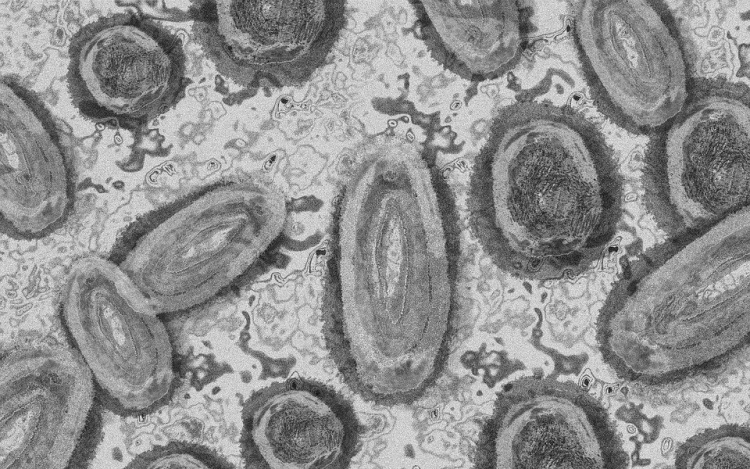

Újabb két embernél igazolt majomhimlő-fertőzést a Nemzeti Népegészségügyi Központ (NNK) a 33. héten - augusztus 15-től 21-ig -, ezzel 64-re nőtt a magyarországi esetek száma.

Az NNK pénteki közlése szerint a 22 és a 31 éves férfi általános állapota megfelelő, kórházi kezelés egyikük esetében sem szükséges; otthonukban tartózkodnak elkülönítve.

Az NNK korábban azt közölte, hogy a betegség általános, nem specifikus tünetekkel - lázzal, hidegrázással, izomfájdalommal, hátfájdalommal, fejfájással, fáradtsággal -, illetve a nyirokcsomók duzzanatával kezdődik, majd 1-3 nappal a bevezető tünetek után bőrkiütések jelennek meg. A kiütések sok esetben először az arcon, majd a tenyéren és a talpon fordulnak elő, de megjelenhetnek a szájnyálkahártyán, a nemi szerveken és a végbél környékén is.